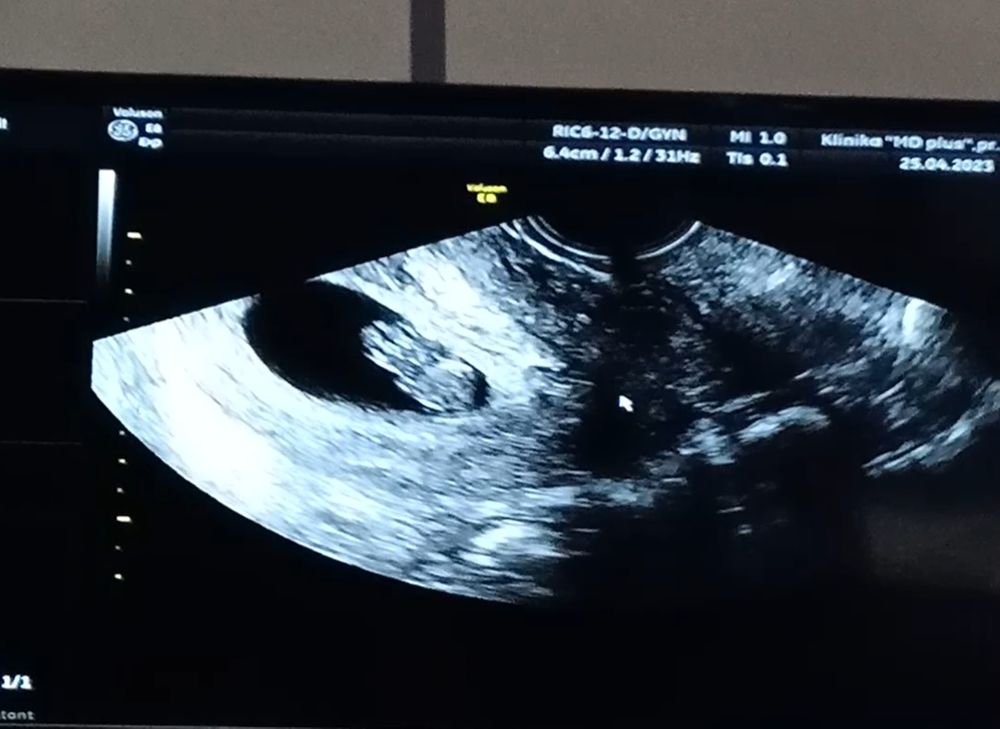

Эхх(в хорошем смысле этого вздоха)... сходила сегодня опять на свидание (УЗИ) к малышу, выросла моя креветка и стала полноценным человечиком ростом в 2см😃 увидела как двигается уже 😇 срок 8+4. Господи храни тех людей которые придумали УЗИ и не дают сойти с ума от невиденья и не знания как растёт твой малыш 😃

25.04.2023